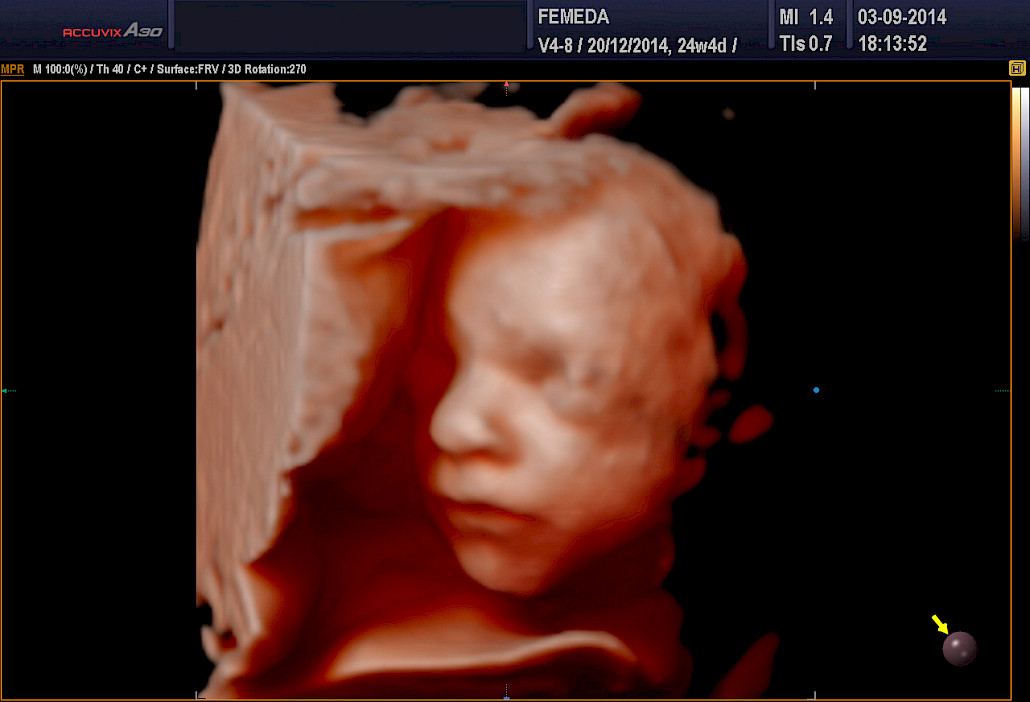

Ehdottomasti molemmat! 3D-tekniikalla tuotetaan staattista neulanterävää kolmiulotteista kuvaa. Se soveltuu sikiön kuvaamiseen, kun halutaan mahdollisimman tarkkaa ja korkealaatuista kuvaa. 4D-tekniikka on tarkoitettu erityisesti sikiön liikkuvaan ja kolmiulotteiseen kuvaamiseen.

3D ja 4D-tekniikat soveltuvat erityisen hyvin sikiön kasvojen anatomian tutkimiseen. Tutkimuksessa poissuljetaan mahdollinen huulihalkio ja kasvojen profiilissa esiintyvät muut poikkeamat, kuten liian pieni leuka. Samalla selvitetään korvien anatomia ja niiden sijainti. Tekniikan avulla selvitetään raajojen asennot, sekä sormien ja varpaiden lukumäärä ja niiden liikkuvuus. Lisäksi tutkitaan koko selkärangan rakenne ja suljetaan pois poikkeamat, kuten puuttuvat lapa- tai olkaluut.

Kuva Femedan 4D-ultraäänitutkimuksesta

Mikä on paras ajankohta 4D-ultraäänitutkimukselle?

4D-tutkimukset voidaan tehdään koska tahansa raskauden aikana. Sikiön rakenne voidaan selvittää kuitenkin parhaiten raskausviikoilla 19-30. Sikiön kasvonpiirteet näkyvät parhaiten raskausviikoilla 22-28. Niukka lapsiveden määrä, epäedullinen sikiön asento, äidin ylipaino tai paksut vatsanpeitteet saattavat vaikuttaa 4D-kuvien laatuun, mutta ne harvoin estävät tyydyttävän arvion saamista sikiön anatomiasta.

Sikiöstä otetut kolmiulotteiset kuvat ovat erittäin tarkkoja ja havainnollistavia – suorastaan kauniita. Kuvauksiin voi tulla millä tahansa raskausviikolla. Tutkimusta ei tarvitse pelätä ja tulevan lapsen isä ja sisarukset ovat myös lämpimästi tervetulleita. Tilanne on usein ikimuistoinen ja ainutkertainen kokemus koko perheelle.